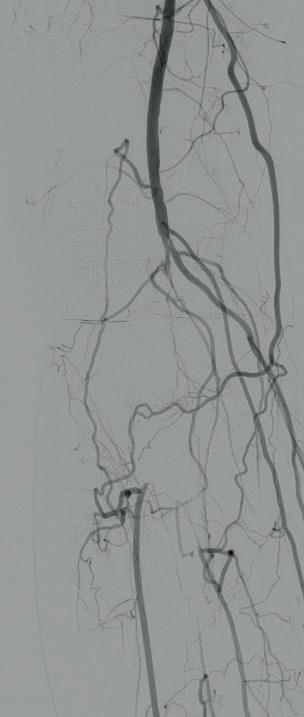

Diagnostic angiogram demonstrated a right popliteal occlusion extending into his proximal tibial vessels (Figure 1). An 0.014” wire was able to easily cross the lesion and pass into the posterior tibial vessel. Intravascular ultrasound (IVUS) demonstrated chronic intraluminal thrombus

with limited evidence of atherosclerosis (Figure 2). A 2.0mm Auryon laser catheter was used to perform a simultaneous athrectomy-thrombectomy (Figure 3). After a single pass, repeat angiogram demonstrated >70% luminal gain (Figure 4). Low pressure (2atm) balloon angioplasty was then performed (Figure 5). Completion angiogram (Figure 6) demonstrated no residual stenosis, with brisk flow into the posterior tibial vessel. The patient developed a palpable posterior tibial pulse, and, at six months, has no claudication symptoms.